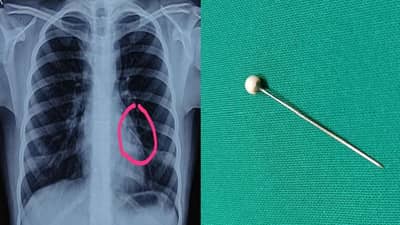

रूग्णालयातील कान-नाक-घसा शल्यचिकित्सक डॉ. शाह यांनी सांगितलं की “या मुलीच्या छातीचा एक्स-रे काढला असता तिच्या छातीच्या डाव्या बाजूला खाली वायूमार्गाच्या भागात पिन आढळून आली. ही पिन शोधण्यासाठी छातीचा सीटीस्कॅन काढण्यात आला. त्यानंतर ब्रॉन्कोस्कोपीद्वारे फुफ्फुसात अडकलेली ही पिन बाहेर काढण्यात आली.”

“श्वसनमार्गात अडकलेली बाहेरील वस्तू काढून टाकण्यासाठी ब्रॉन्कोस्कोपी केली जाते. भूल देऊन ही प्रक्रिया करावी लागते. ब्रॉन्कोस्कोपी वापरून फुफ्फुसातील वायुमार्गापर्य़ंत प्रवेश मिळविण्याची ही प्रक्रिया आहे. साधारणतः एक तास ही शस्त्रक्रिया सुरू होती. या शस्त्रक्रियेनंतर अवघ्या तासाभरात मुलाच्या प्रकृतीत सुधारणा दिसून आली,” अशी माहिती डॉ. शलाका दिघे यांनी दिली.